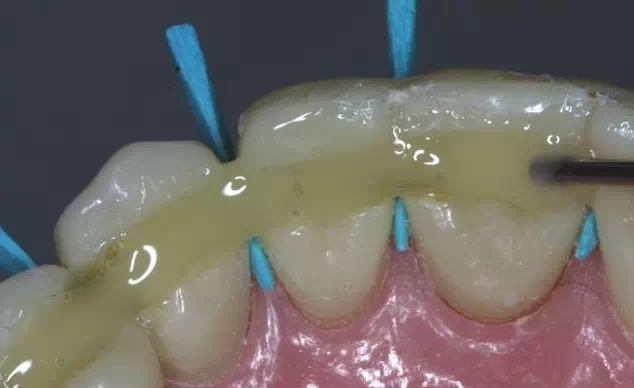

這是牙周病常規(guī)的治療方法,清除或控制臨床炎癥和致病因素,去除病因,消除炎癥。包括口腔衛(wèi)生宣教、充填齲洞、口腔潔治刮治、牙體牙髓治療、咬合調(diào)整、去除不良修復(fù)體、藥物治療(輔助手段,局部用藥效果好)、拔除治療效果不佳的牙周病患牙等。

牙周炎發(fā)展到一定階段時(shí),僅采用基礎(chǔ)治療難以取得較好療效,必須通過(guò)適時(shí)而合宜的手術(shù)治療挽救患牙,才能保持牙周組織健康,延長(zhǎng)患牙在口腔內(nèi)的壽命,維持牙列的完整性,促進(jìn)全身健康。其手段包括齦下刮治、根面平整、牙周翻瓣術(shù)、牙齦切除術(shù)、牙周夾板固定術(shù)等。